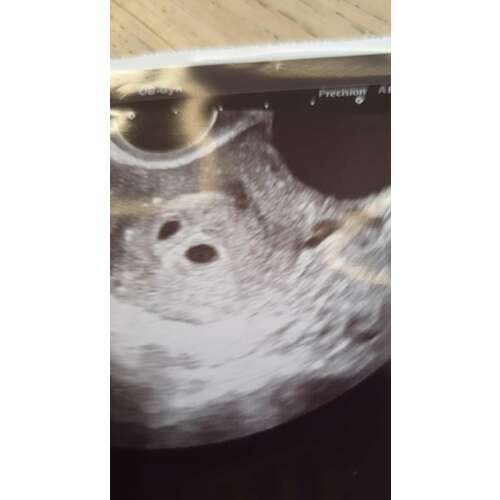

Ik had gister mijn eerste echo met 6+5 en ik heb ook een cyste, maar mijn gyn gaf aan dat dit de eierstok is geweest die een eitje heeft afgegeven en waarvan ik zwanger ben gebleven. Deze blijft en wordt een soort cyste die progesteron afscheid zegmaar. Het is dus wel nodig begreep ik , maar zo vanzelf weg moeten gaan.